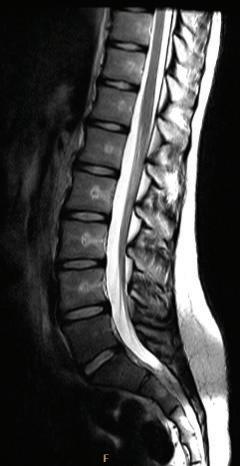

In T1 image sequences, fluid has low signal and appears dark on the image. Lipids and other specific tissues may have high signal and be bright (T1 hyperintensity). With contrast enhancement by a gadolinium-based contrast agent, tissue that contains the agent has high signal on T1-weighted images. In T2-weighted images, fluids (or tissue with high water content) have a high signal and appear bright (T2 hyperintensity) (Fig. 1-22 and Table 1.2). PD (proton density) sequences are neither T1 nor T2 weighted.

FIGURE 1-22 T1-weighted and T2-weighted axial MR lumbar spine images. Note that the cerebrospinal fluid (CSF) is hyperintense (bright) in T2 image and hypointense (dark) in T1 image.